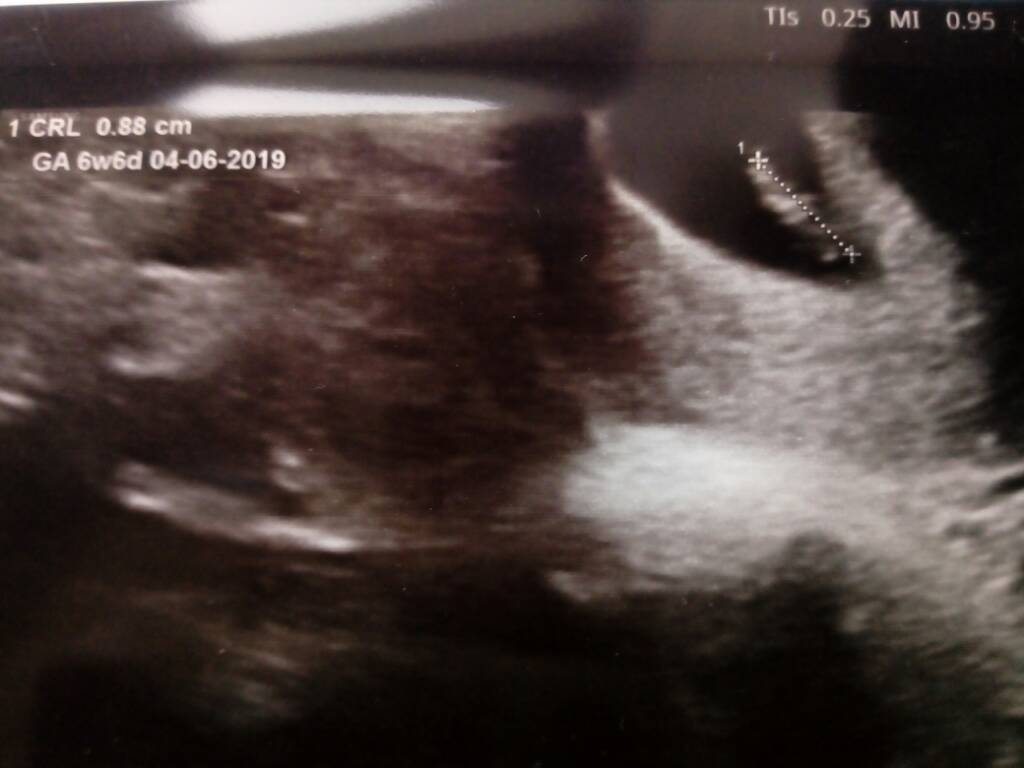

Ja właśnie po stresujacym badaniu, bo w usg dopochwowym nie mógł znaleźć serduszka, ale maluch tak sie ułożył, że o dziwo przez usg brzuszne było widać piękne serduszko[emoji7]

Termin wg om 02.06

Termin wg usg 04.06

Więc prawie się pokrywają daty[emoji3] Jestem przeszczesliwa!!!